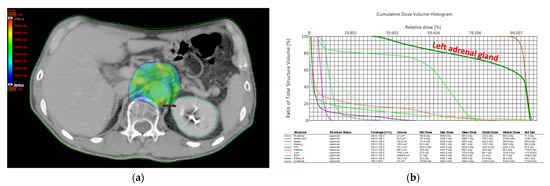

3.2.2. RT Dosimetry